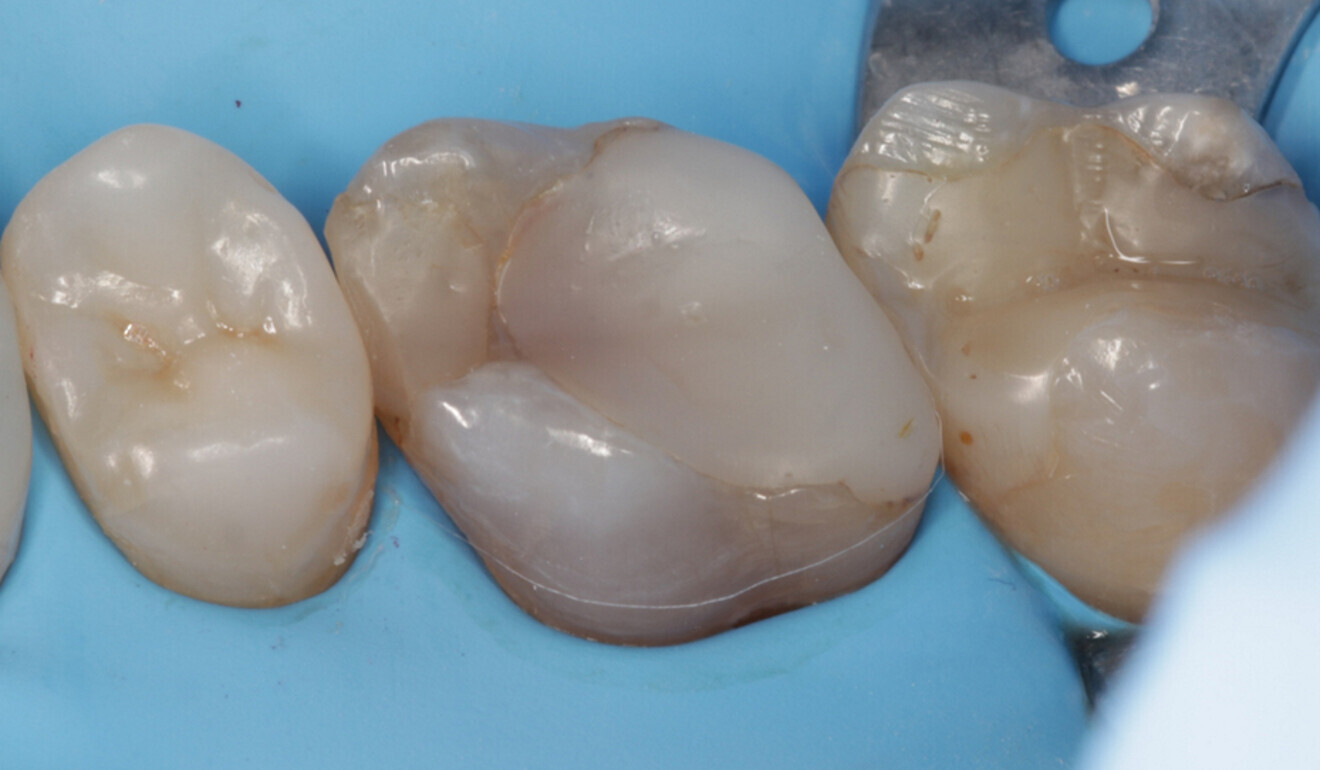

Fig. 16: Occlusal surface after surface modelling with CLEARFIL MAJESTY ES-2 Universal and initial polishing, occlusal view. (Image: Kuraray Noritake Dental)